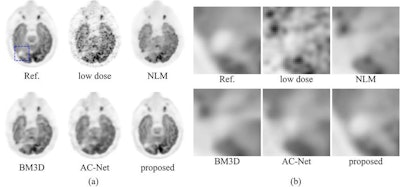

Comparison of the Stanford deep-learning method with existing low-dose PET enhancement algorithms. The full-dose reference PET image is shown on the upper left, followed by the 200x lower-dose image and the results of different image denoising/restoration methods such as non-local-mean (NLM) denoising, block-matching and 3D filtering (BM3D) denoising, a previously proposed deep autocontext convolutional neural network (AC-Net), and the proposed Stanford model. The Stanford researchers believe visual comparison of both the entire image (a) and the zoomed-in regions (b) show the superior image quality restoration of their algorithm. All images courtesy of Enhao Gong.The algorithm was able to produce comparable image quality to conventional studies at more than 99% lower radiotracer dose reduction levels for PET, and even 99.5% lower dose for brain FDG-PET /MRI, according to the researchers.